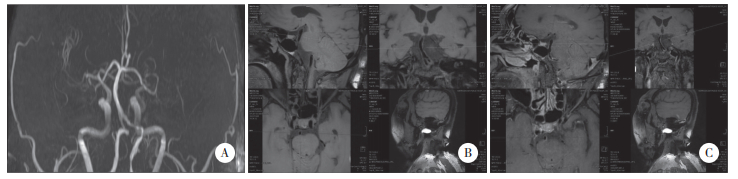

并发组BA直径、BA长度、VA颅内段长度长于未并发组,BA分叉高度分级≥2级、BA偏移度分级≥2级比例高于未并发组(P<0.05),见表 2,图 1、2。

| A, MRA revealing a tortuous and dilated vertebrobasilar artery; B, imaging of the vascular wall revealing eccentric thickening of the local wall of the VA; C, enhanced imaging of the vascular wall showing significant enhancement of the wall. 图 2 VBD并发后循环ACI患者MR-VWI图 Fig.2 MR-VWI image of VBD patients with posterior circulation ACI |